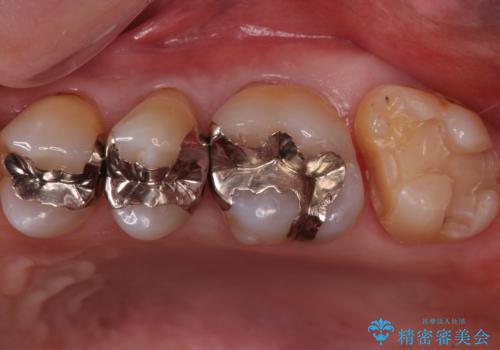

奥歯の虫歯 ゴールドインレーでの修復処置

- メンテナンスで3年ぶりにいらっしゃた患者様です。

検査の結果虫歯が確認されたため、治療を進めることとなりました。

- 左上7 ゴールドインレー 77,000円費用は治療当時の料金となります